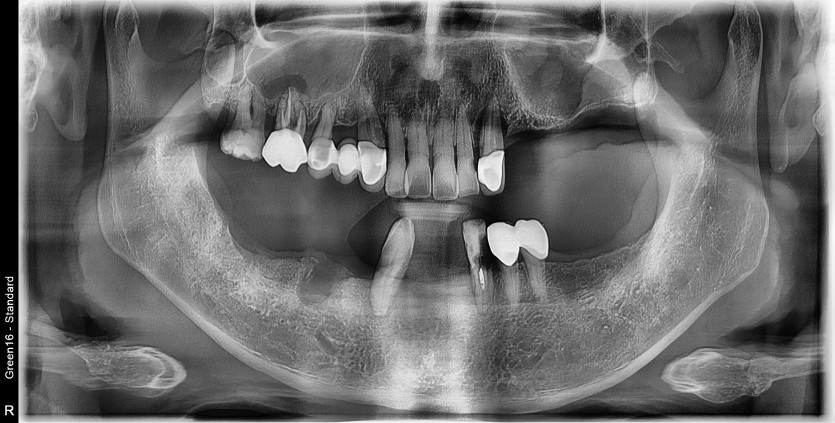

전체 임플란트 증례입니다.

18개의 임플란트로 완성하였습니다.